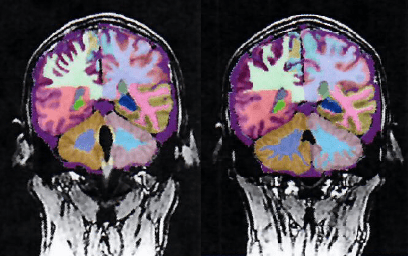

After taking Cover Three daily for 2 months, a fMRI showed improved blood flow to the frontal lobes of Todd's brain. A healthy frontal lobe is key for brain health. This is the “control panel” of our personality and our ability to communicate. It is the part of the brain that controls important cognitive skills, such as problem solving, memory, emotional expression, language, sexual behaviors, and judgment.

Results showed improvements in all neurocognitive parameters with an 18% increase in Attention, 14% increase in Verbal Memory, and a 9% increase in Reaction Time.